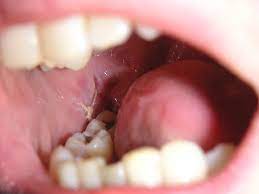

When your wisdom tooth erupts, it is normal to experience discomfort.

Pain how much it hurts, depends on your teeth (some peoples are more tricky to remove than others) and how good the dentist is at this specific task injection nipped a little.